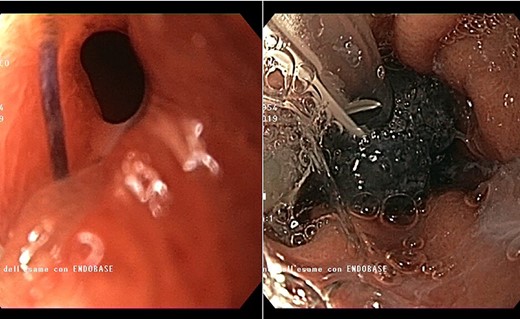

Endoscopic view of the prepyloric ulcer perforation (left) and intraluminal placement of E-VAC (right)

high PCR (291 mg/L) and the CT scan showed a right hydropneumothorax (Fig. 1). The first suspicion was an anastomotic leak and, in consideration of the hemodynamic instability and the severe septic state, the patient was submitted to emergency surgery. We performed a thoracoscopy with intraoperatively esophagogastroduodenoscopy which revealed a perforated prepyloric ulcer of the gastric tube. We therefore proceeded with accurate pleural toilette and closed the perforation with surgical stiches. At the end of the procedure, two thoracic drains and a naso-gastric tube with the distal end near the suture were placed. An additional naso-duodenum enteral feeding tube to ensure adequate nutrition was positioned. The patient was admitted in the Intensive Care Unit and supported with inotropic drugs, broad-spectrum antibiotics and proton pump inhibitor therapy. In the following days, the patient’s conditions improved allowing his extubation and his transfer to the surgical ward. Unfortunately, imaging and endoscopic check revealed a recurrent perforation. Considering the failure of the conservative approach, we decided to start the E-VAC Therapy on his 21st post-operative day (POD), using the Eso-SPONGE® System (B. Braun Surgical, S.A. Carretera De Terrassa, Rubi, Spain), firstly placed intraluminal because of the reduced size of the wall defect (Fig. 2). After three E-VAC replacements we did not observe any endoscopic or radiologic improvements. Moreover, on his 35th POD, due to a new impairment of vital signs, the patient underwent a second surgical treatment, with a new pleural toileting and another unsuccessful attempt of closing the conduit defect surgically. Considering the prolonged hospital stay, we placed a feeding jejunostomy. We proceeded with a new attempt of E-VAC, this time by placing it intracavitary (Fig. 3 and Fig. 4). The E-VAC was changed every 48–72 hours, reshaping the dimension of the sponge every time according to the size of the cavity. We observed a progressive reduction of the cavity size during the seriated endoscopic and CT evaluation. Considering the continuous improvement of patient’s clinical condition we discharged him after 84 days of hospitalization, with the E-VAC in place. The device replacement was carried on twice a week as an outpatient treatment, until its definitive removal (Fig. 5). The total duration of the therapy was 37 days with 13 E-VAC intracavitary interventions. Seven days after the device removal we performed an upper gastrointestinal X-Ray with oral contrast that showed no contrast medium leakage. The patient was therefore allowed to resume oral intake. At 6 months follow up the patient was in good clinical conditions; radiological test and endoscopy showed no abnormalities.